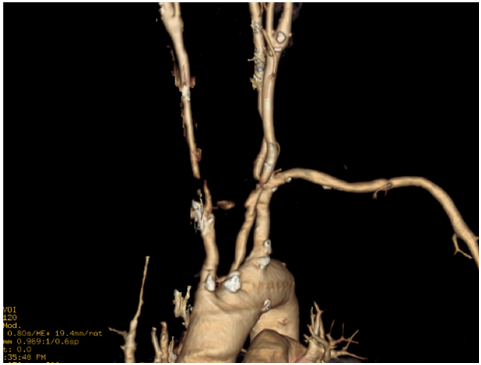

Cranioencephalic computerized tomography excluded acute ischemic lesions.CDS revealed severe stenosis of the innominate artery (PS 38 cm/s) (Figure 1), occlusion of right vertebral artery, total flow inversion of the right internal carotid artery (ICA) (Figure 2), partial endosystolic flow inversion of right CCA (Figure 3) and low amplitude anterograde flow of right external carotid artery, no significant lesions were found on the left carotid axis. Computerized tomography angiography (CTA) excluded significant carotid lesions and revealed pre-occlusive stenosis of the innominate artery by a calcic lesion (Figure 4).Surgical approach consisted of ultrasound-guided puncture of right brachial artery and surgical exposure of right CCA. Brain protection was achieved by direct clamping of the common carotid artery and subsequently carotid and axillary retrograde endovascular access was obtained. Placement of 6F introducer on brachial artery and 8F on right CCA (Figure 5). After pre-dilatation with a 4x40mm balloon (Admiral Xtreme™, Medtronic), a kissing stent technique was performed with a 6x59mm covered stent (AdvantaV12™, Getinge) on the right CCA and 7x57mm balloon-expandable stent (Visi-Pro™, Medtronic) on the right subclavian artery. At the end of the procedure direct expulsion of eventual embolic material was performed prior to declamping and a good permeability of the revascularized arteries was verified (Figure 6). Clamping time was under 1minute. The postoperative period was uneventful and patient was discharged 3days later.

Figure 4 CTA 3D reconstruction showing the innominate lesion.